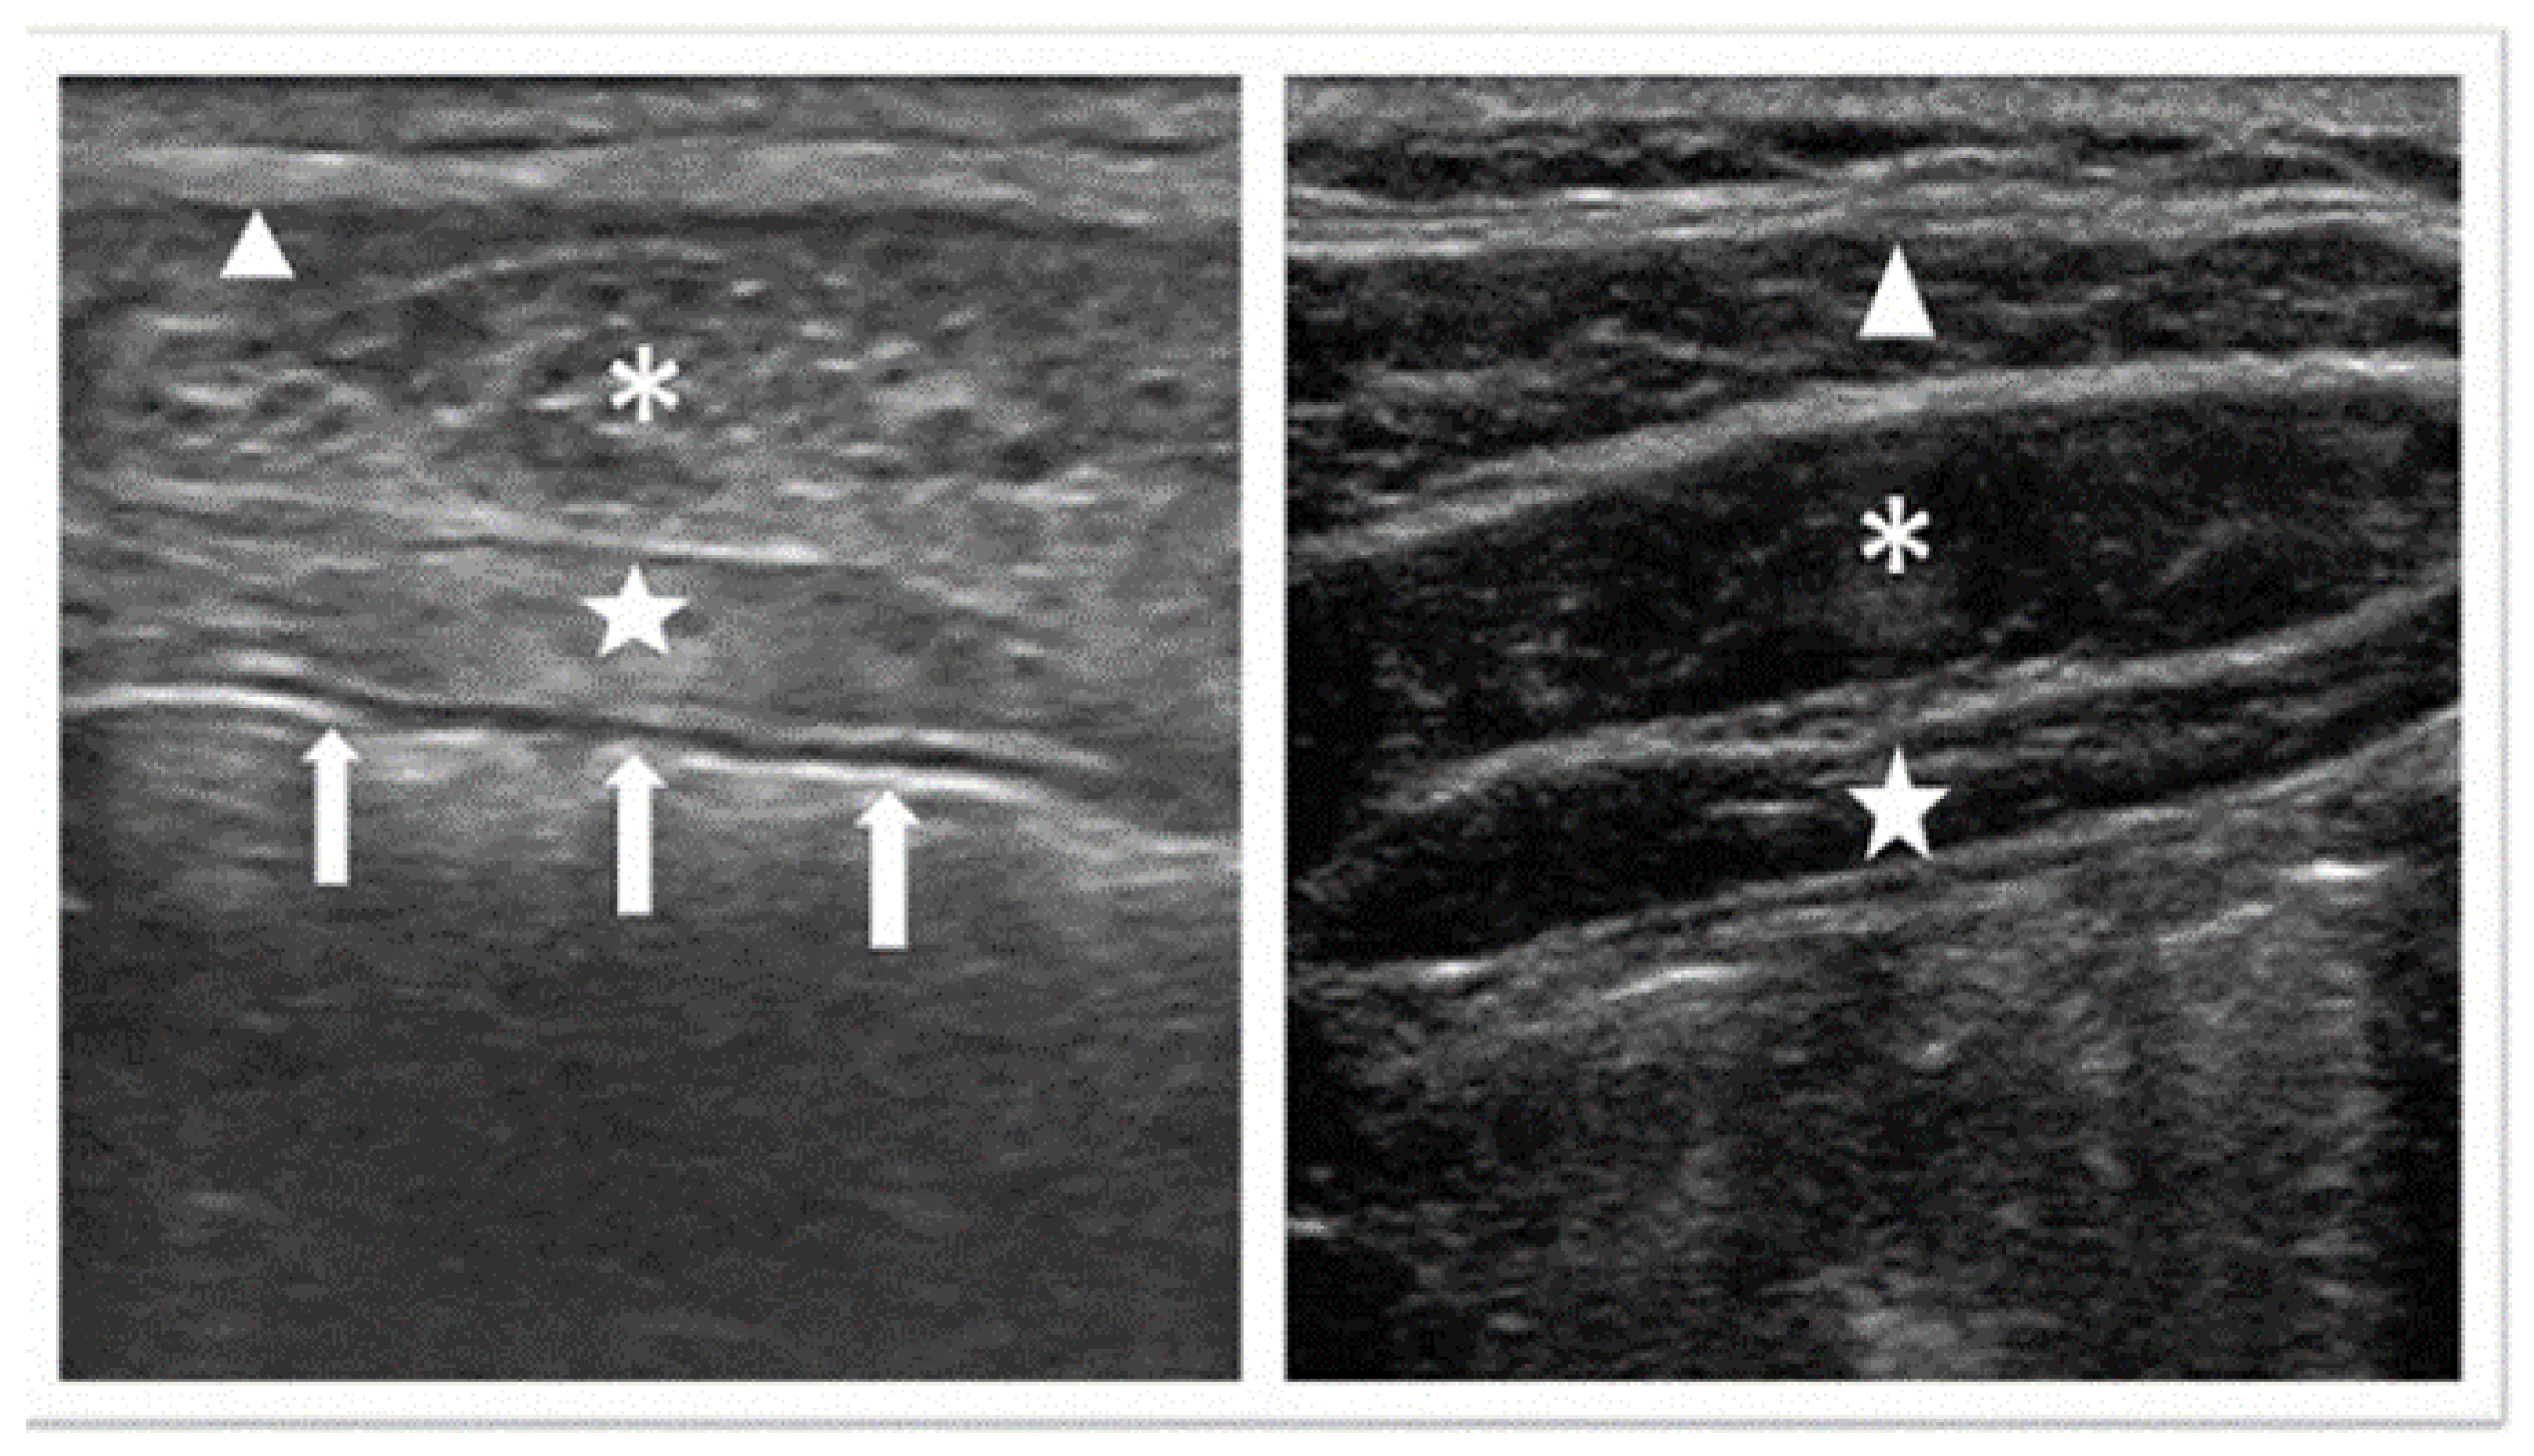

- Kuroiwa, K.K.; Nakazawa, M.; Nishizawa, M. Lanthanum carbonate hydrate causes artifacts on ultrasound. J. Anesth. 2015, 29, 974. [Google Scholar] [CrossRef]

| Kuroiwa et al. | 2015 | UL + CT | Hyperecchoic signal in the intestines. | Intestines | NR | Anesthesiologists who perform transesophageal echocardiography and the abdominal US need to be familiar with the characteristics of LCH. | Lanthanum carbonate hydrate causes artifacts on ultrasound (nih.gov) |